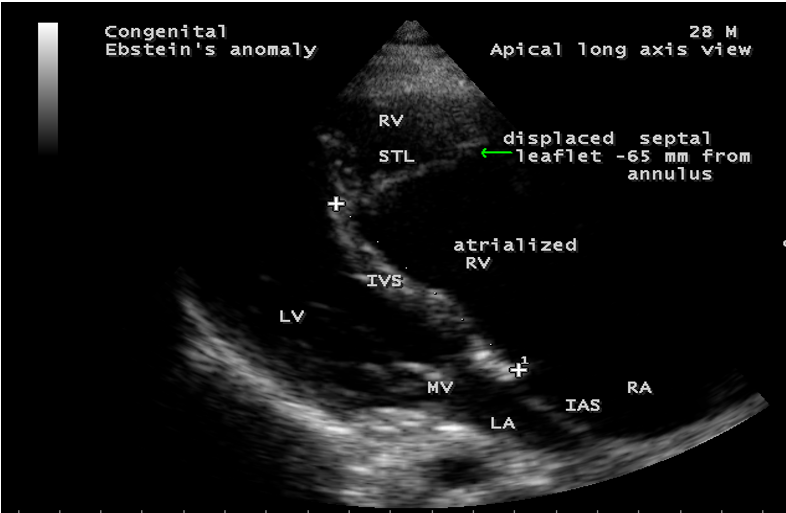

A 28-year old male presented with cyanosis and auscultation revealed a ‘sail sound’ ( loud tricuspid component of first heart sound due to increased tension developed by the large anterior leaflet as it reaches the limits of its systolic excursion- an important sign of anterior leaflet mobility), a ‘cadence’ quality of quadruple rhythm due to wide splitting of first and second sounds ( due to complete right bundle branch block), atrial and ventricular filling sounds (summation of these sounds due to prolonged PR interval). ECG revealed the features of Ebstein’s anomaly as shown in Figures 11 and 12. X-ray chest revealed the Ebstein’s configuration as shown in Figure 13. 2D echocardiography revealed a ‘sail-like’anterior tricuspid leaflet forming a ‘muscular curtain’ in between the inflow and trabecular parts of the right ventricle as an ‘imperforate membrane’ with a ‘pinhole’communication, associated with a muscular VSD (ventricular septal defect) in the proximal, atrialized compartment of right ventricle suggesting an ‘atretic” (‘imperforate’) Ebstein’s anomaly as shown in Figures 14 to 27.

Echocardiographic features Echocardiography is the diagnostic test of choice for Ebstein’s anomaly and the first echocardiographic diagnosis was reported by Lundstrom in 1969. The first diagnostic criteria for Ebstein’s anomaly using a multi-crystal two-dimensional system was defined by Hagan in 1974 [33] and they were able to recognize the apical displacement of the septal tricuspid leaflet and an elongated anterior tricuspid leaflet with increased excursion. The septal leaflet of the tricuspid valve attaches chiefly to the ventricular septum , but part of its basal attachment is to the posterior wall of the right ventricle [34] and it normally exhibits a slight but distinct apical displacement of its basal attachment to the central fibrous body compared to the mitral valve. The distal displacement of septal origin of tricuspid valve seems to be the best echocardiographic criterion as the characteristic sign for Ebstein’s anomaly and the degree of maximal displacement in normal hearts varies considerably with a mean difference of approximately 6 mm with mitral valve. To define the anatomic severity of Ebstein’s anomaly, four-chamber view is the best to demonstrate the apical displacement of septal tricuspid leaflet [35]. The ratio between the mitral-to-apex distance and the tricuspid-to-apex distance varies from 1 to 1.2 in normal subjects and 1.8 to 3.2 in patients and it is 3.6 as in Figure 18 with Ebstein’s anomaly. The true distance in the level of insertion of atrioventricular valves is obtained by substracting the tricuspid-to-apex distance from the mitral-to-apex distance with a mean value of 27.25 ± 12 mm in patients with proven Ebstein’s anomaly and it is 60 mm as shown in Figure 18 compared to reference group (5.7 ± 2 mm). Kambe and coworkers calculated the distance between both atrioventricular valves directly as a mean value of 21 mm with a range of 14 to 32 mm [36]. A maximum difference in the level of valve insertion of >15 mm in children and >20 mm in adults is discriminated between normal and Ebstein’s anomaly [37],[38]. Despite this fact, a patient with an ‘unequivocal’ Ebstein’s malformation can be encountered in whom the diagnosis cannot be made with certainity solely on the basis of apical displacement of the septal tricuspid valve leaflet. Occasionally, the leaflet attaches to the trabecular part rather than the inlet part of the septum, the conventional four-chamber view will not reveal any septal insertion as shown in Figures 28 and 29.

The anterior tricuspid leaflet is not involved in the process of downward displacement, it may be abnormally inserted occasionally and Shiina, et al documented the apical displacement of anterior tricuspid leaflet in 14% of cases echocardiographically [39]. The anterior leaflet forms a large, sail-like intracavitary curtain as in Figures 14, 25 and contains muscular strands instead of consisting entirely of a fibrous membrane as in the normal tricuspid valve [40]. It is potentially mobile with a brisk sail-like movement as shown in Figure 21 to 24 [41], free bloating with a ‘whipping motion’ across the right ventricular outflow tract (RVOT) as shown in Figure 26 and in some cases, the movement is restricted due to its adherence to the ventricular wall as in Figure 1 and 2, 4 and 9. It is often fenestrated, may in part be musculaized , inserting into the trabeculations of the right ventricle (RV) as in Figure 28 and rarely, the anterior leaflet forms an ‘atretic’ membrane that spans the midportion of the right ventricular cavity as in Figure 16.

Ebstein’s original case was an example of obstruction at the tricuspid orifice by a membrane dividing the right ventricle into two halves as shown in Figure 16 of a 28-year old cyanotic male with ECG and X-ray characteristics as in Figure 11 to 13. suggesting an advanced spectrum of Ebstein’s malformation , necessitating RV exclusion techniques such as Starnes’ procedure. The florid case of Ebstein’s anomaly with the insertion of leaflet tissue along with ventricular walls as a ‘blanket’ as in Figures 28 and 29 in a 30-year old cyanotic male may go for an initial palliation with bidirectional Glenn shunt (cavopulmonary anastomosis). The other variants of moderate degree of leaflet tethering with varying degrees of regurgitation, but an intact basal leaflet attachments with atrioventricular junction as in Cases 1 and 2 may need a definite repair. In Ebstein’s mitral valve as in Figure 32 in a 10-year old boy, the downward displacement of functional annulus > 0.8 cm/m2 is not particularly striking and tends to affect the septal leaflet (anterior mitral leaflet) alone. The valve is thickened and mildly regurgitant due to rheumatic involvement rather than an anatomic cause.